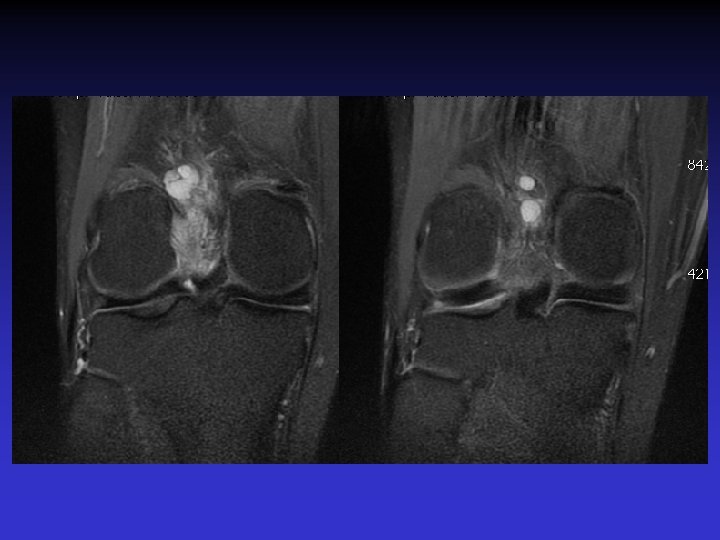

ATTEINTE BILATERALE • Non exceptionnelle • Concomitante ou décalée dans le temps

Mme S… 60 ANS DROIT

Mme S… 60 ANS GAUCHE